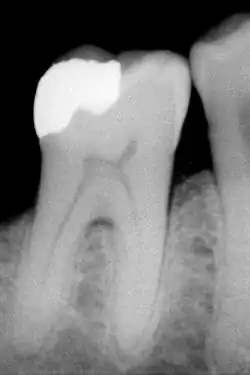

Dentální amalgámy

Používají se jako velmi odolná výplň zubu po odstranění zubního kazu. Jde o slitinu rtuti se stříbrem, mědí a cínem v poměru 1 dílu rtuti ku 1 dílu ostatních kovů. Ve světě se ročně spotřebuje do zubních amalgámů kolem 270 tun rtuti, z toho asi 70 tun připadalo na 15 zemí EU před jejím rozšířením o nové členské státy.[3]

Dentální amalgám musí splňovat řadu přísných kritérií:

- Rychlost tuhnutí musí být taková, aby lékař měl dostatek času plombu do zubu správně zasadit a mechanicky upravit, současně by však již po hodině až dvou měla být natolik tvrdá, že ji pacient může používat (kousat na ošetřený zub). Celkově amalgám tvrdne po dobu přibližně 24 hodin.

- Během tvrdnutí nesmí docházet k velkým rozměrovým změnám amalgámu – při expanzi by hrozilo rozlomení zubu, při zmenšení objemu by plomba vypadávala.

- Amalgám musí být co nejvíce chemicky odolný vůči prostředí v lidských ústech, aby nedocházelo k uvolňování rtuti a zbylých kovů do organismu.

V dnešní době se hodně diskutuje o náhradě zubních amalgámů, protože si vědci nejsou jisti, nakolik poškozují zdraví lidí.[4] Proto se hledají náhrady jako například plastické polymery.